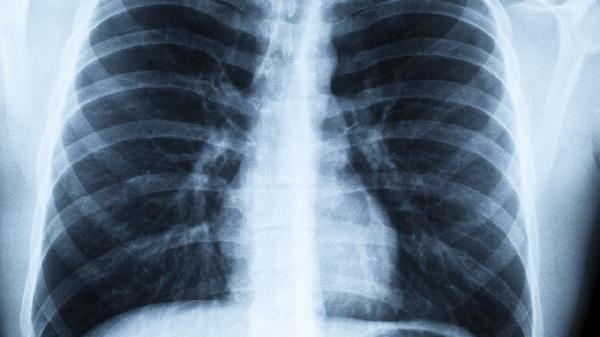

肺炎聽診可聞及肺部濕啰音,胸片顯示肺部浸潤影;感冒一般無肺部異常體征。肺炎患者呼吸頻率增快>20次/分,部分出現(xiàn)口唇紫紺等缺氧表現(xiàn)。